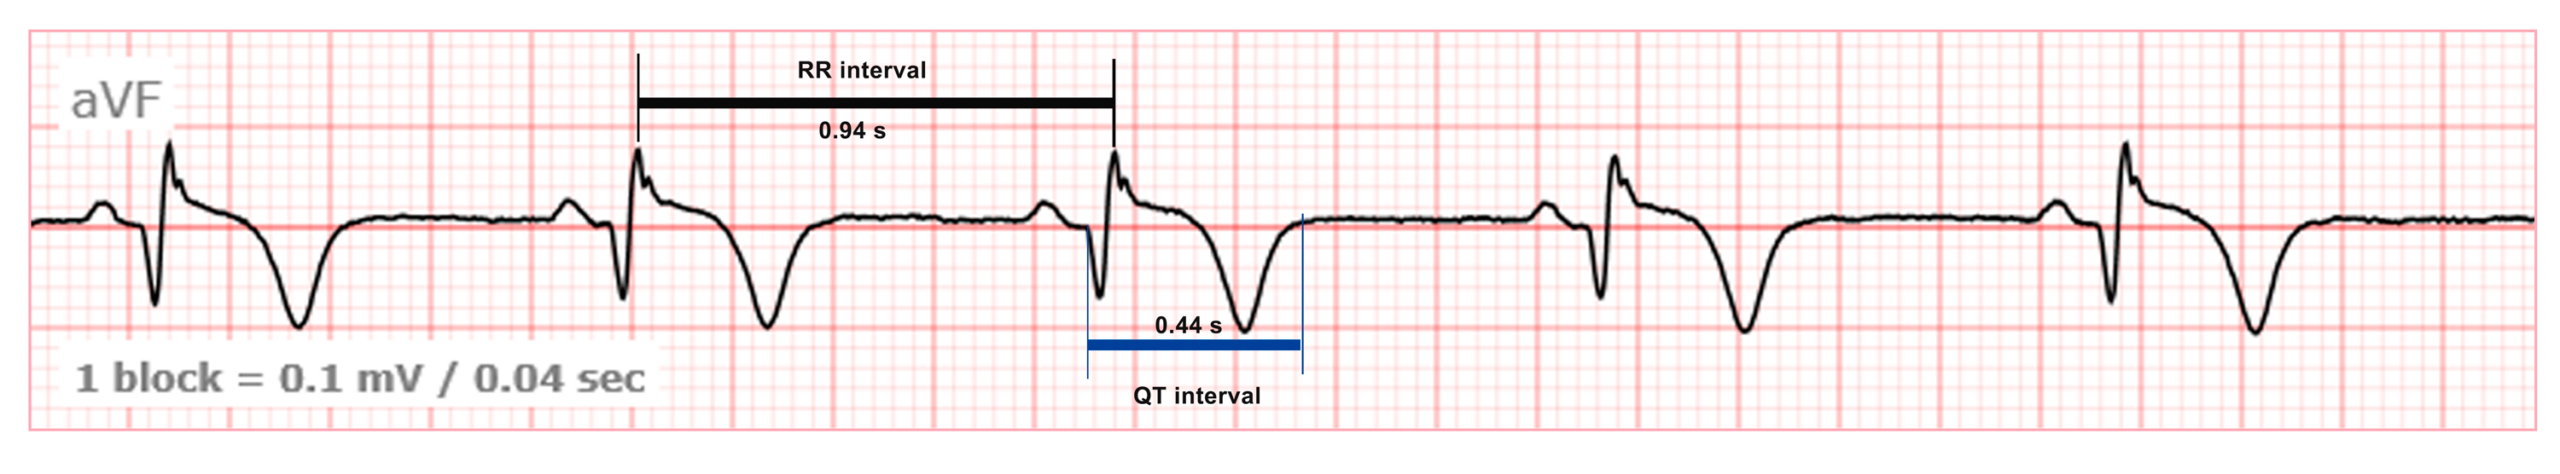

We determine the duration of the RR and QT intervals.

This ECG belongs to a male patient! A QT interval of 0.44 (10×0.04) s is within normal limits, but it requires correction for heart rate. RR 0.94 (23.5 × 0.04). QTc = QT / √RR = 0.44 / √0.94 = 0.453 s, which slightly exceeds the normal limit of 0.45 s.